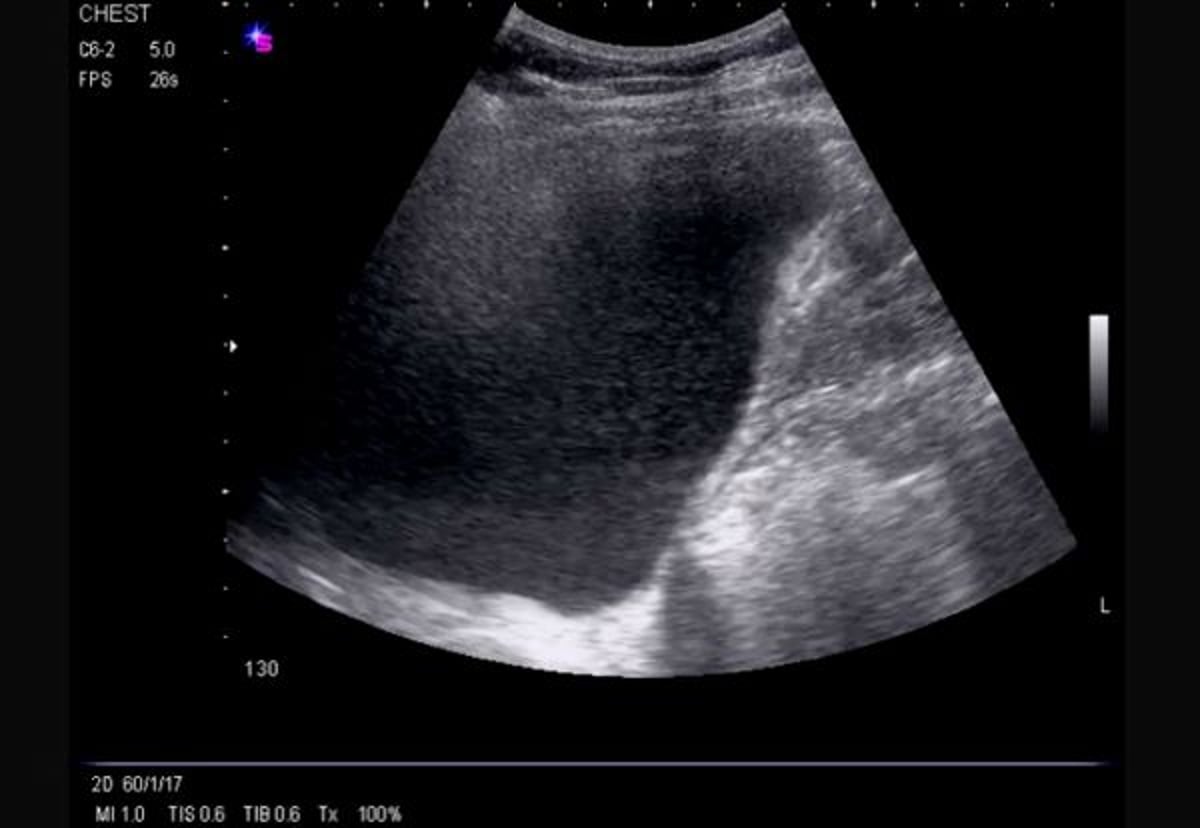

Ecografía lateral torácica (derecha)

Esta ecografía muestra un derrame libre masivo del lado derecho, ecogénico, que causa inversión del hemidiafragma.

Image courtesy of Najib M. Rahman, BMBCh MA (oxon) DPhil.